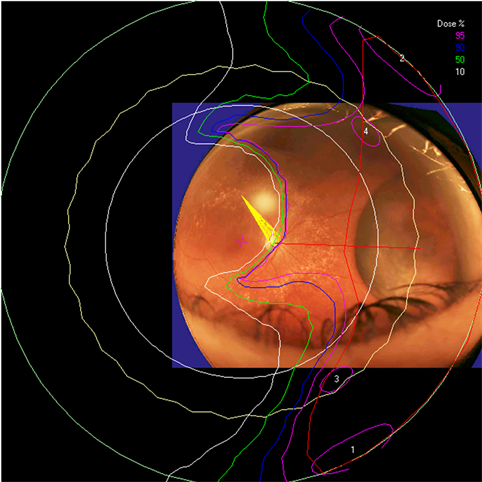

Clinical relevance of the extended distal range in silicone was studied for impact in EYEPLAN treatment planning software, including cases in which tumors were in close proximity to the optic disc/nerve and macula as well as cases in which anterior ciliary body tumors were treated. To demonstrate the necessity of the dosimetry measurement in silicone oil, we present an example of a patient with a ciliary body tumor in the right eye that is relatively amelanotic and involves the iris root but does not involve the angle. The dimension of the tumor is 13 × 8 × 8.7 mm3 (tumor height of 8.7 mm). Figure 5(a) shows the beam’s-eye-view (BEV) of the treatment plan, using gaze direction having polar and azimuth angle of (30˚, 135˚). The patient is looking towards the upper right-hand corner of the box (up and out). The range of the beam is 14.7 mm and SOBP is 16 mm. The aperture contour around the tumor represents the 50% isodose line. The optic nerve and macula are behind the tumor and receiving no proton dose, while some portion of the lens is within the 50% isodose line. This can be clearly seen from Figure 5(b) which shows the treatment plan in the lateral view. Figure 6(a) shows the dose distribution in the fundus view for a normal eye and figure 6(b) shows the dose distribution in the fundus view for a silicone oil filled eye, with adjusted proton range. Figure 7(a) and Figure 7(b) are the respective dose volume histograms (DVHs) for the two scenarios of a normal water-equivalent eye (7a) and a silicone-filled eye with potential proton range impact (7b). In this case as seen from Figure 6(a) and Figure 7(a), optic disc, macula and optic nerve gets 0 dose in the normal eye. If the eye were to be filled with silicone oil, the range of the beam would increase by 2mm. In that case as seen from Figure 6(b) and Figure 7(b), the dose to 50% area of the disc would increase by 50% of the total dose (i.e. 28 GyE in this simulation). A length of 0.4 mm of the optic nerve would receive 50% of the total dose (Figure 7(b)) as compared to the treatment plan if the eye is filled with water (Figure 7(a)). The doses to the structures of the eye in two scenarios are summarized in Table 3.

Figure 6. The isodose lines are displayed on the polar view of the back of the eye. The fundus image is superimposed on the polar view. The macula lies at the center of this view (represented by a cross), and the rest of the eye is “unfolded” around it. The optic nerve and disc are also shown near the center of the eye. The concentric circles represent the equator, ora serrata, lens and limbus of the cornea (moving from the back to the front of the eye). (a) dose distribution for normal eye (b) for eye filled with silicone oil.

The potential adjustments to distal range and penumbra in the context of silicone oil filled eyes are important for clinical eye treatment planning. The ocular melanoma case example presented in this study demonstrates that for example eyes with a thick ciliary body tumor may appear to receive zero dose to the optic nerve and disc. However once planning model modifications are made to reflect the potential impact of silicone oil on the range of the proton beam, the disc and nerve dose increase. In the silicone oil modified plan of the same eye, 50% of the area of the disc would receive 50% of the total dose and a length of 0.4 mm of the optic nerve would receive 50% of the total dose. Such clinically relevant information is essential for treatment planning, dose volume analysis, and informing the clinician and patient.